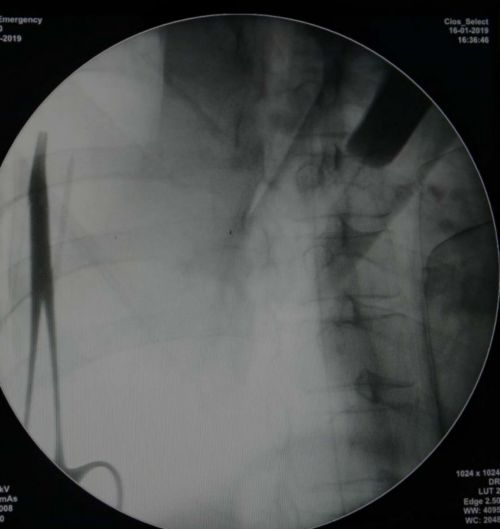

张宇副主任医师为患者施行c臂引导下鞘内镇痛泵植入术。

影像学定位鞘内导管植入理想脊髓节段。